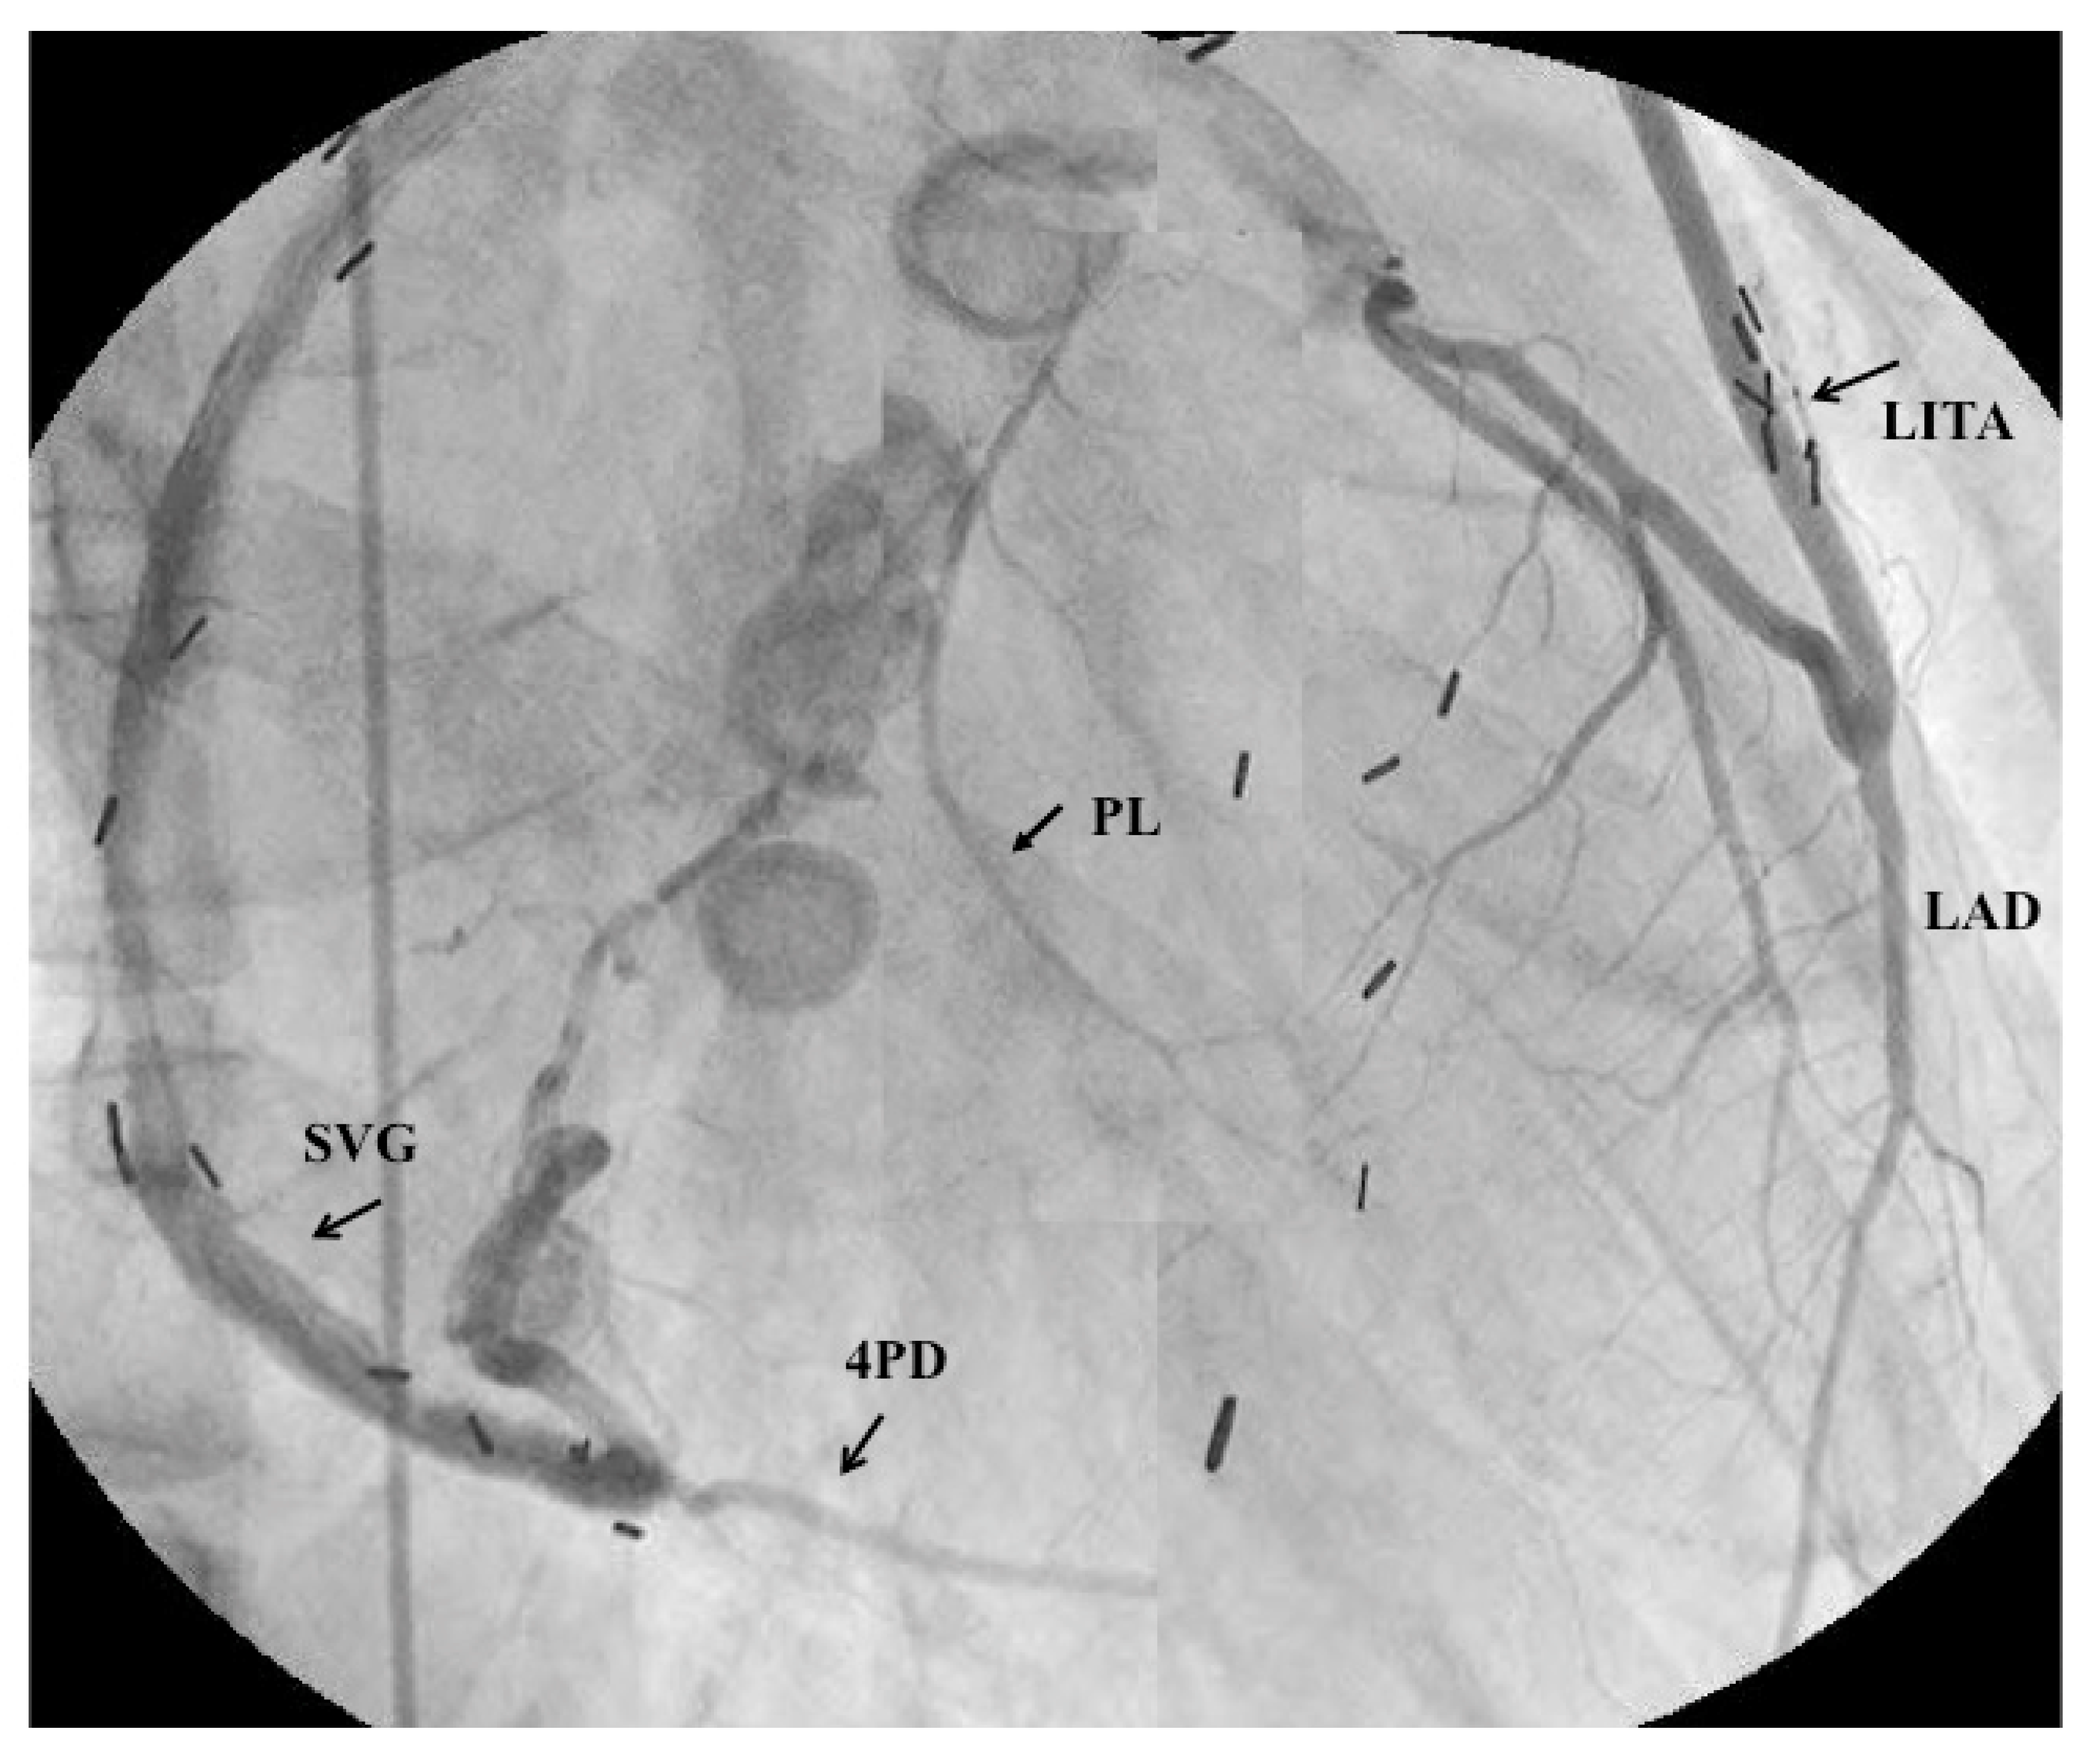

- Tsuda, E.; Fujita, H.; Yagihara, T.; Yamada, O.; Echigo, S.; Kitamura, S. Competition between native flow and graft flow after coronary artery bypass grafting. Impact on indications for coronary artery bypass grafting for localized stenosis with giant aneurysms due to Kawasaki disease. Pediatr. Cardiol. 2008, 29, 266–290. [Google Scholar] [CrossRef]

- Tsuda, E.; Kitamura, S.; Kimura, K.; Kobayashi, J.; Miyazaki, S.; Echigo, S.; Yagihara, T. Long-term patency of internal thoracic artery grafts for coronary artery stenosis due to Kawasaki disease: Comparison of early with recent results in small children. Am. Heart J. 2007, 153, 995–1000. [Google Scholar] [CrossRef] [PubMed]

- Tsuda, E.; Kitamura, S. The Cooperative Study of Japan. National survey of coronary artery bypass grafting for coronary stenosis caused by Kawasaki disease in Japan. Circulation 2004, 110 (Suppl. II), II61–II66. [Google Scholar] [CrossRef] [PubMed]

- Kitamura, S.; Tsuda, E.; Kobayashi, J.; Nakajima, H.; Yoshikawa, Y.; Yagihara, T.; Kada, A. Twenty-five-year outcome of pediatric coronary artery bypasss surgery for Kawasaki disease. Circulation 2009, 120, 60–68. [Google Scholar] [CrossRef] [PubMed]